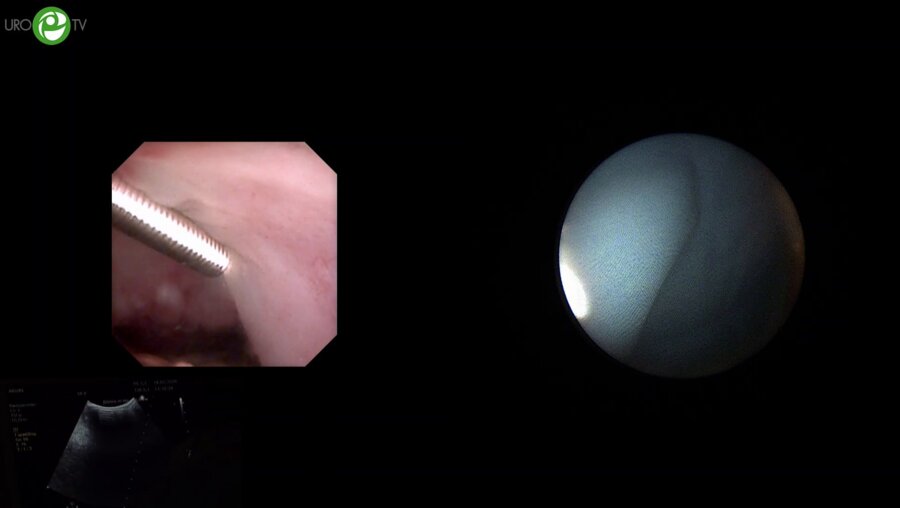

Цистит. Срываем маски. Выпуск №30. БЦЖ-ассоциированный цистит. Особенности клинической картины и лечебной тактики при химико-индуцированных циститах